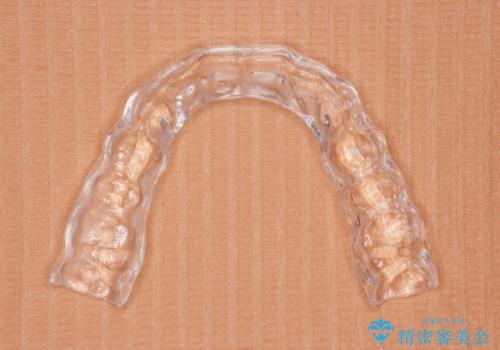

ナイトガードによる歯の予防

ナイトガード(自費)を作製しました。

保険のナイトガードに比べて自費のナイトガードは割れる心配がないです。

また噛み合わせの歯と調整をして全体に均一に当たるように調整を行うので噛んだとき力が全体的に分散して歯の負担も減ります。